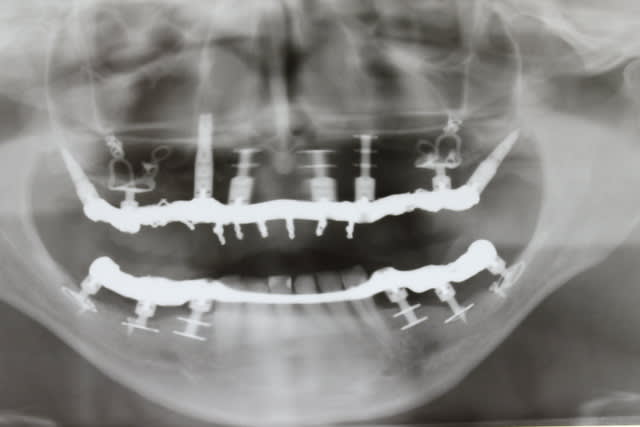

Bon un petit travail réalisé à main levée et sans aucune forme de guide...

C'est plus de la biologie, c'est de la mécanique!

Mais vu la quantité d'os disponible, il ne restait pas 36 solutions. Pas facile comme cas.

Ca tiendra certainement, mais a la pano c'est pas beau, surtout avec cette qualité.

Par contre, en bas la barre.. J'espère que la patiente aura une bonne maintenance.

La crête s y prêtait pas vraiment et je préfère poser des plaques en enfouissant la partie distale ds le trigone, disquer en remontant ds le trigone peu aisé et très hémorragique mais c est le prix à payer pour avoir une plaque qui s intègre bien à cet endroit

Alors oui j ai préféré poser 4 monodisk

Pour la barre, aucune gêne : elle est posée comme une barre de stellite mais contrairement au stellite cette barre ne va jamais comprimer la muqueuse par enfoncement puisque les implants sont rigides

Pas dit qu on ne la conserve pas pour le définitf mais de tte façon je compte laisser ces provisoires au moins deux ans

Oui sûr que vu le capital osseux résiduel, sauf à greffer massivement, il y avait peu de choix thérapeutiques

1. les extensions distales càd ne pas occuper le site osseux le plus distal au maxillaire, ça va tjs ds le mur à terme ( 5 à 7 ans )

2. tu ne vois pas ce prémaxillaire : c est de la lame de couteau de partout saut où j ai posé l axial en 13 doc pour poser des cylindres là il te faudrait greffer aussi et en plus édenté depuis l âge de 17 ans au niveau du bloc incisif suite à traumatisme... Donc non seulement tu as pas de hauteur et en plus une petite lame de couteau... Comment on greffe ça proprement pour y poser à coup sûr 6 cylindres??? Le patient a 46 ans càd en pleine vie professionnelle et a bcp apprécié de rester seulement 3 j sans dents... Comment tu fais si tu greffes??? Le mieux étant de ne porter aucun amovible sur le greffon le tps de la prise???

Bon plus sérieusement ces implants que tu appelles des selles sont des diskimplants à plaque d ostéosynthèse. On les les reçoit plans et il faut les les déformer pour les adapter à la conformation nécessaire au niveau du zygoma, de la zone canine sup ou de la zone du trigone. Ensuite on les bloque avec des vis d ostéosynthèse et on les entoure de biomat afin de provoquer un gros cal osseux autour , ce qui soutiendra la plaque à terme car les vis ne servent qu au blocage primaire...